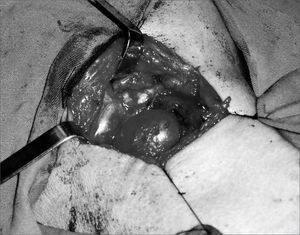

CASE REPORTOur patient was a 45 year old female, housewife, seen in May of 2002, complaining of dysphonia for 40 days, associated with snoring. She did not smoke or had any pulmonary disorder, nor had she had prior laryngeal problems. During physical exam, she had a mass in her right cervical region (Figure 1) and during the laryngoscopic exam she had a bulging near the ventricular fold and the right aryepiglottic fold (Figure 2). We ordered a CT scan and an MRI (Figures 3 and 4) which revealed a large cystic lesion filled with air, thus confirming the diagnosis of laryngocele. In late June of 2002, while she underwent preoperative exams, she was having intense dyspnea and required urgent tracheotomy. As her clinical signs stabilized, she underwent resection of the lesion by an external via (Figures 5 and 6). She progressed without complications in her postoperative, with full symptoms improvement and normal laryngoscopic exam (Figure 7).